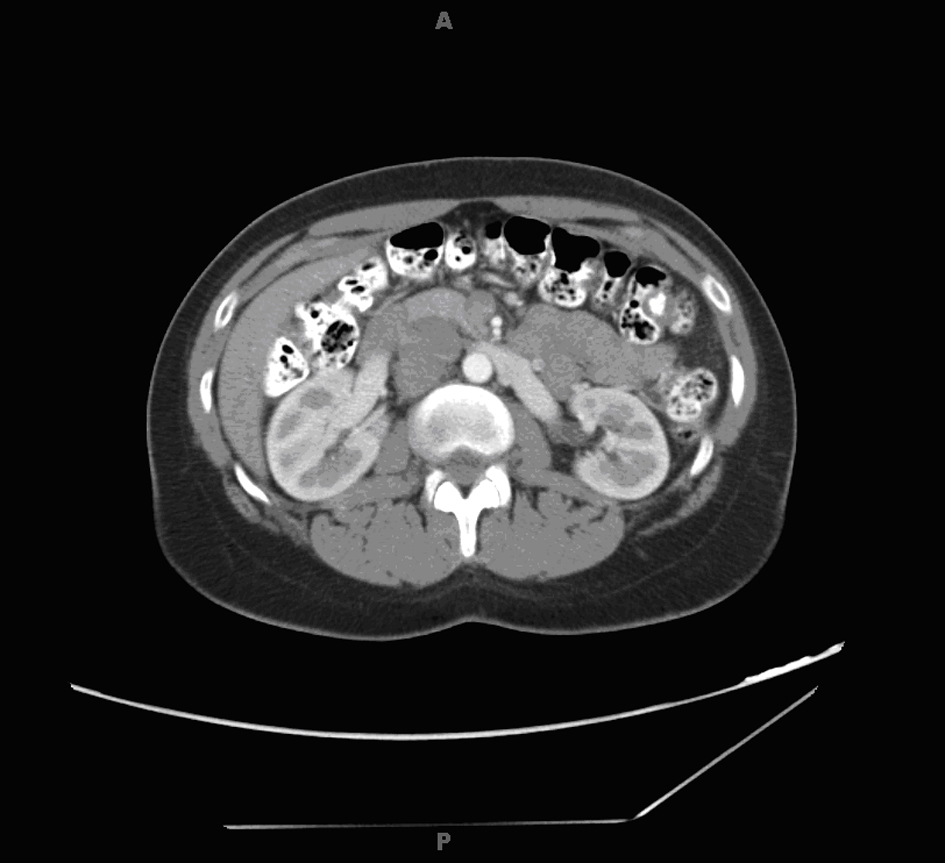

Radiology work up included a CT scan of the abdomen and pelvis which revealed a 4.6 × 3.6 × 3.9 cm right paracaval mass extending to the right renal vein and artery alongside effacement of the inferior vena cava (Fig. 1). In addition, an enlarged and lobulated uterus was visualized in the pelvis.

![]() Click for large image | Figure 1. Abdominal computed tomography scan showing right paracaval mass. |